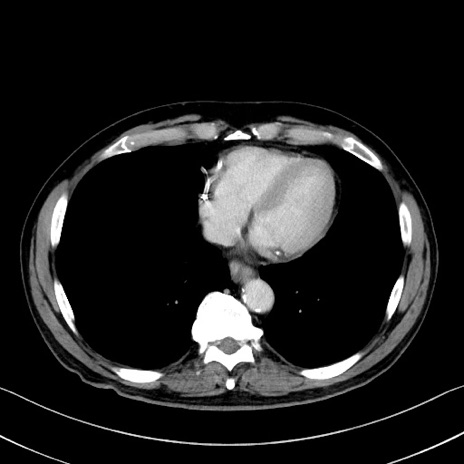

症例35(横断像)

【症例】70歳代 男性

【主訴】腹部膨満、嘔吐

【現病歴】昨日より腹部膨満感出現。本日増悪し、仙痛出現。嘔吐あり、受診。

【既往歴】糖尿病、胆摘後

【身体所見】BP 149/80mmHg、HR 74/min、BT 35.9℃、腹部:膨満、軟、圧痛なし。腸雑音減弱あり。上腹部正中切開瘢痕あり。

【データ】WBC 13500、CRP 1.72